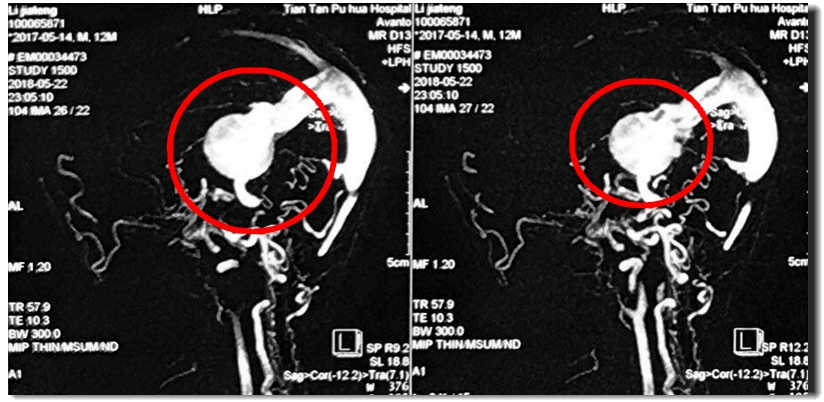

检查发现,小飞的脑子里出现了这么一个大家伙,体积巨大,几乎占到颅脑的十分之一。小飞的爸爸妈妈带着他从省医院又来到北京。这时已经是5月21日了。这时候小飞不时出现呕吐,头痛,身体僵直的癫痫症状。

5月22日晚,小飞被推进北京天坛普华医院的手术室。这是根据影像形成的3D图形,下面这根粗粗白白的是脑动脉,上面这两个球是静脉在压力之下形成的“气球”。原来,负责给小飞大脑供血的动脉和静脉悄悄地搭在一起不说,还通了一个洞。动脉里的血本来要给大脑输*养送**料的,在这里开了小差,直接钻到了静脉里。可是静脉哪儿承受得了动脉的压力,直接被吹大了。血管壁吹弹可破,随时可能爆裂。一旦爆裂,小飞的生命马上就会出现危险。

这是手术前后的造影图。可以看出来,术前血液都跑到两个大球里,大脑供血几乎看不到。而术后,大黑球消失,瘤子所处的大脑区域有了明显的血液供应,枝杈丰富,几乎能听见血液在此前干瘪的血管中欢快地奔腾。